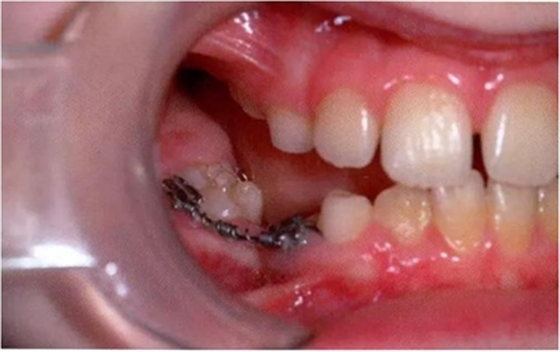

當(dāng)下沉乳牙需要拔除時(shí),應(yīng)當(dāng)注意這樣的牙齒由于跟牙槽骨有粘連,所以會(huì)有骨折的傾向。應(yīng)當(dāng)考慮使用無(wú)創(chuàng)拔牙技術(shù),即在使用牙鉗拔除之前先設(shè)法松解破壞牙槽骨與粘連牙之間的骨性結(jié)合。嚴(yán)重下沉或者難以入路的牙齒有必要使用外科手術(shù)拔牙。如果鄰牙傾斜可能引起嚴(yán)重的牙弓長(zhǎng)度喪失,對(duì)合牙伸長(zhǎng)和阻礙繼承恒牙萌出的話,也應(yīng)當(dāng)拔除下沉乳牙。當(dāng)使用正畸裝置時(shí),可以開(kāi)展間隙,改進(jìn)入路。因此下沉乳牙的管理也可以被納入到一個(gè)全面的治療計(jì)劃中(圖10 )。這樣就可以允許有更直接的下沉牙拔除入路,甚至可以促進(jìn)下沉牙的萌出并避免進(jìn)一步的干預(yù)。

圖10:臨床照片展示使用固定可調(diào)正畸裝置糾正傾斜的下頜磨牙